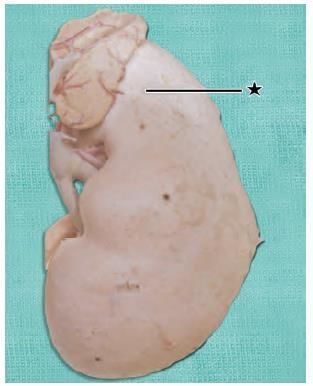

A child was brought to the hospital by his father with complaint of fever, low backache and persistent flexion of the hip joint. He had a history of Spine TB in the past. On examination child has an inguinal swelling. Identify the marked muscle responsible to be involved in this pathology: (NEET-PG 2021)